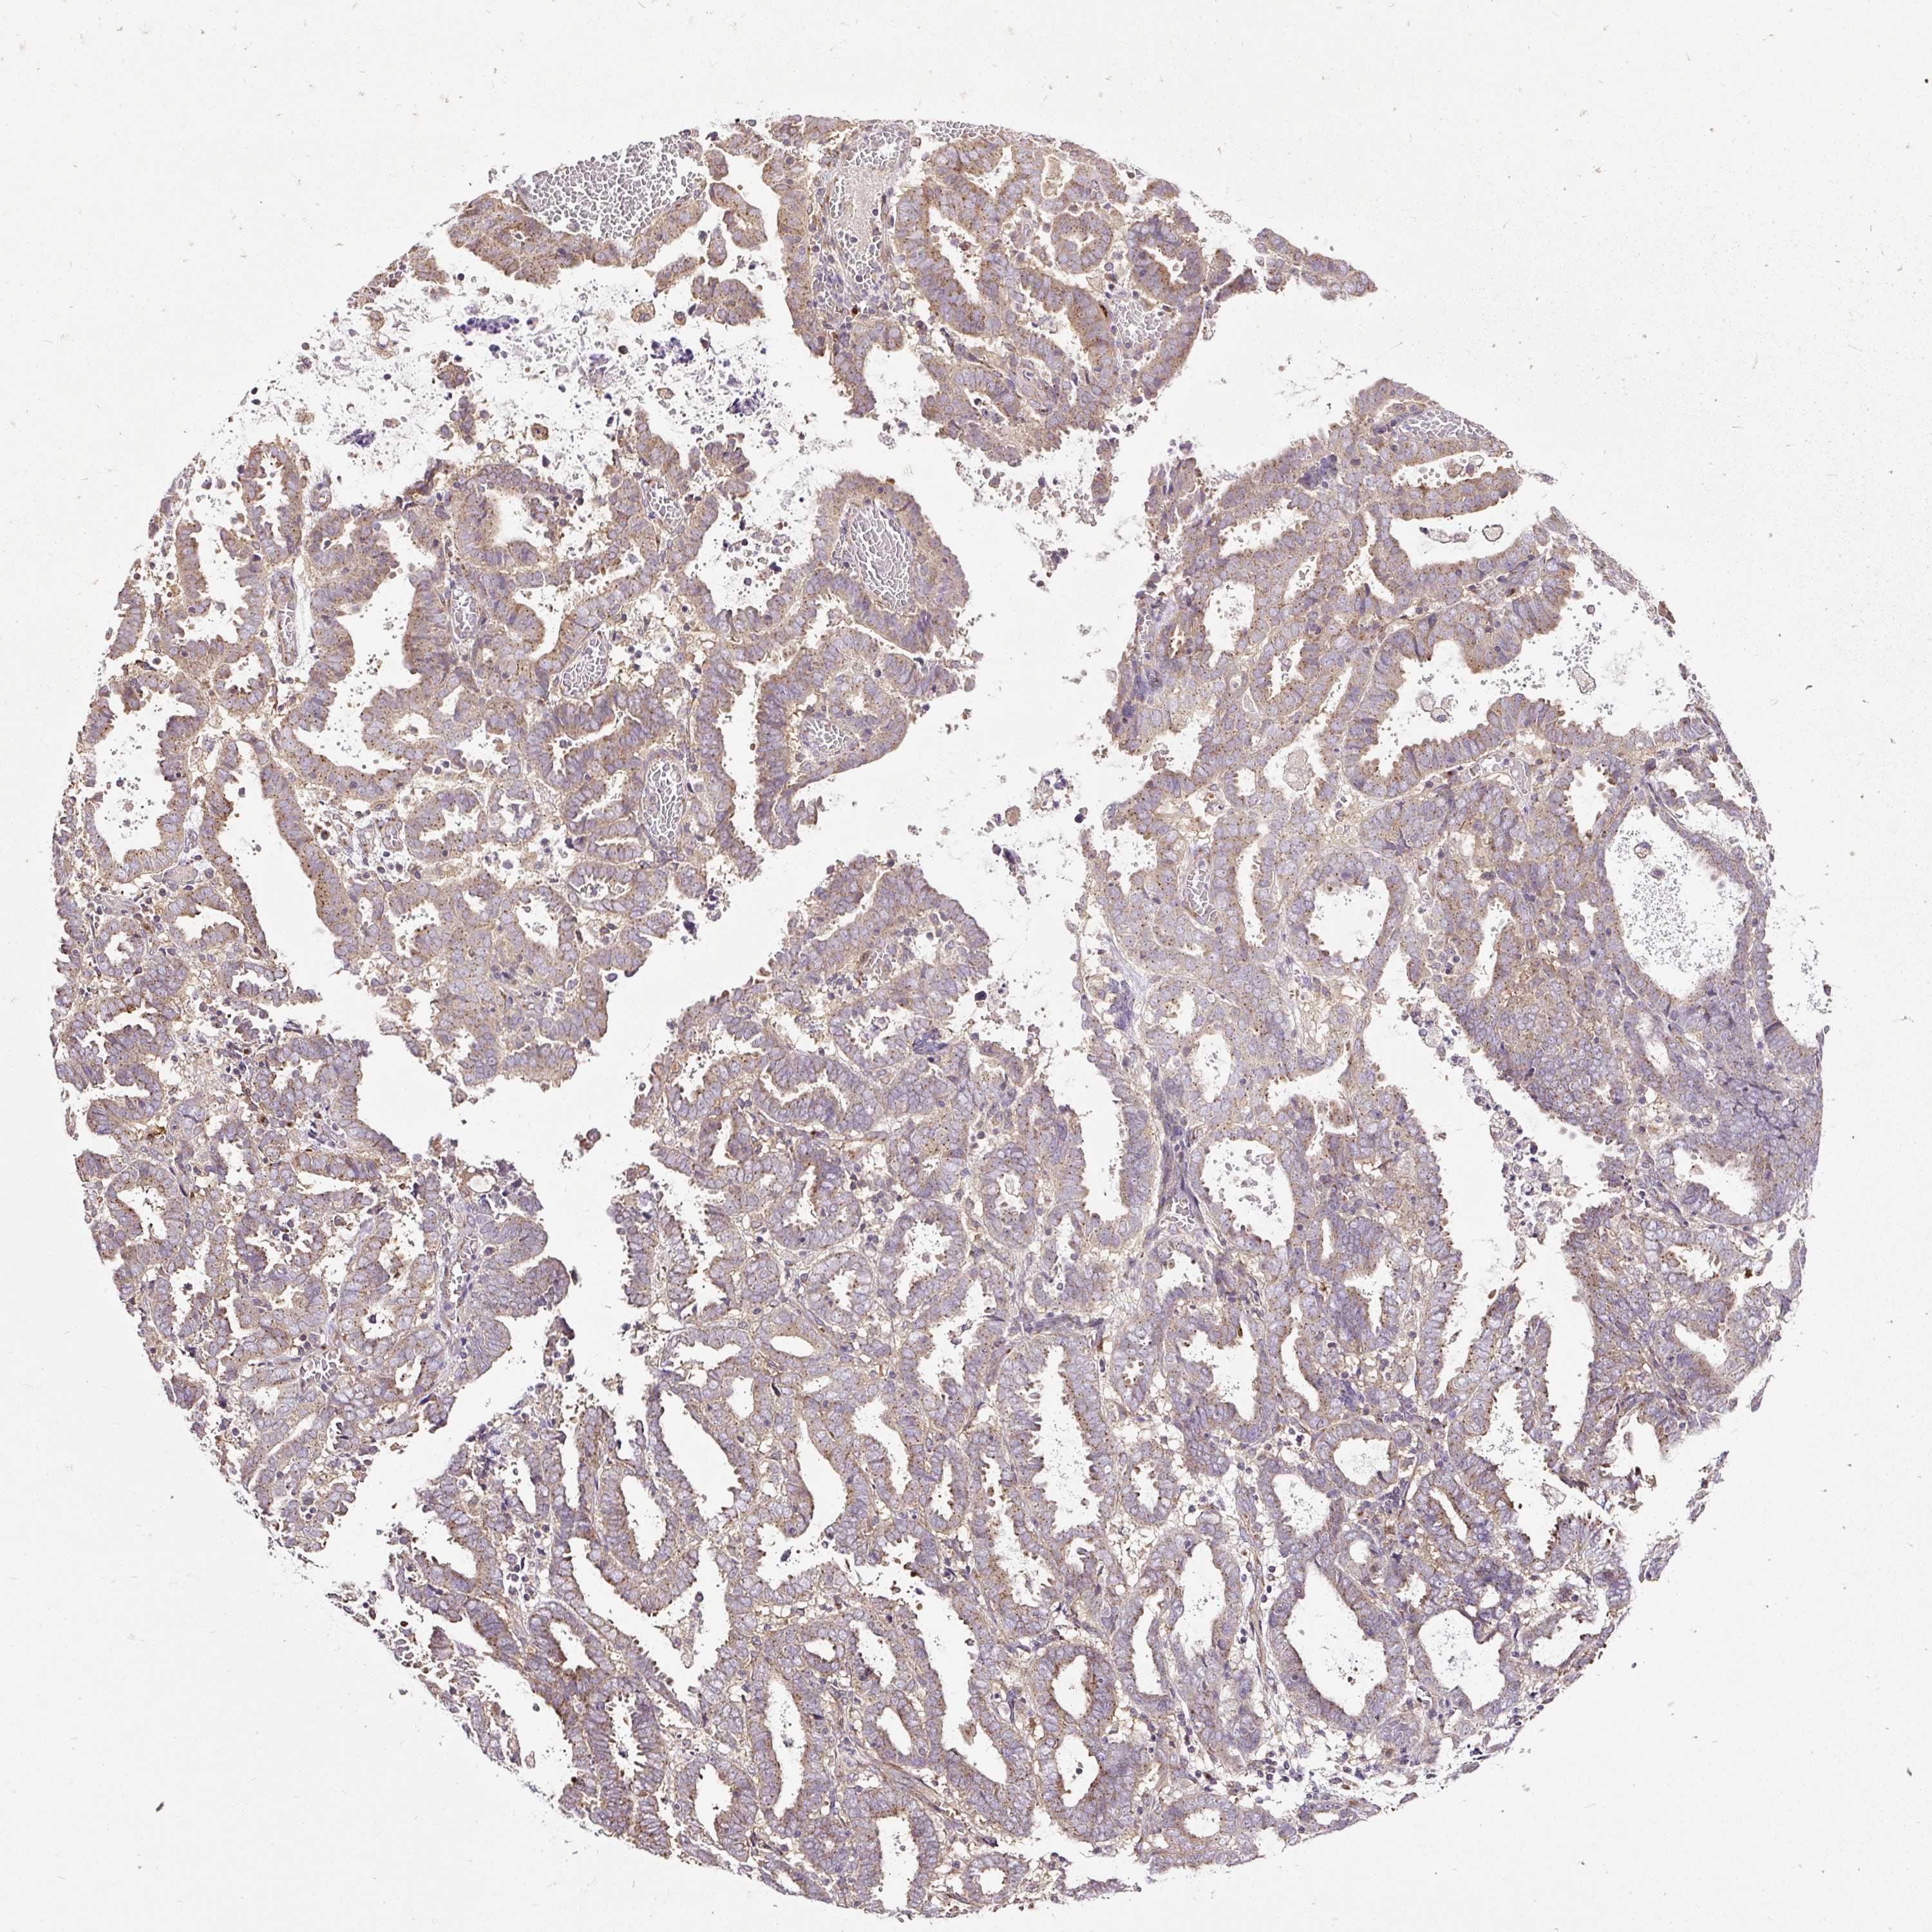

ENDOMETRIAL CANCER - Protein expressioni

A mouse-over function shows sample information and annotation data. Click on an image to view it in a full screen mode. Samples can be filtered based on level of antibody staining by selecting one or several of the following categories: high, medium, low and not detected. The assay and annotation is described here.

Note that samples used for immunohistochemistry by the Human Protein Atlas do not correspond to samples in the TCGA dataset.

Antibody stainingi

Antibody staining in the annotated cell types in the current human tissue is reported as not detected, low, medium, or high, based on conventional immunohistochemistry profiling in selected tissues. This score is based on the combination of the staining intensity and fraction of stained cells.

Each image is clickable and will lead to virtual microscopy that enables deeper exploration of all samples and also displays staining intensity scores, fraction scores and subcellular localization as well as patient and tissue information for each sample.

Antibody HPA029449

Antibody CAB055509

Staining

High

Medium

Low

Not detected

Intensity

Strong

Moderate

Weak

Negative

Quantity

>75%

75%-25%

<25%

None

Location

Nuclear

Cytoplasmic/membranous

Cytoplasmic/membranous,nuclear

Adenocarcinoma, metastatic, NOS